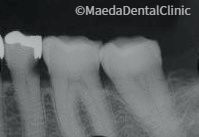

詰め物の下の虫歯

違和感に気付いて初めて受診されました。レントゲン写真では神経の近くまで進行している虫歯のため、大きく歯を削らなければなりません。